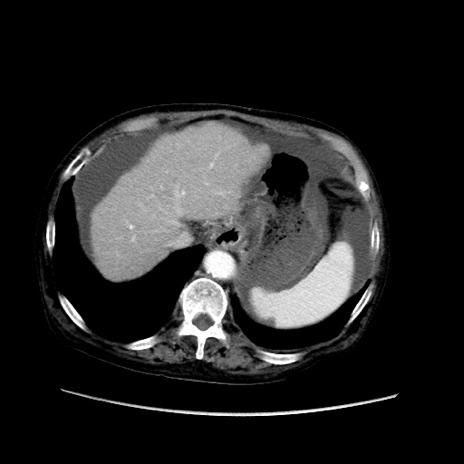

症例31(横断像)

【症例】80歳代 女性

【主訴】腹部膨満感

【現病歴】他院にて肝硬変にてフォロー中。1週間前から便秘、腹部膨満感、臍部腫瘤あり受診となる。

【既往歴】肝硬変

【身体所見】腹部膨隆あり、皮膚変化なし、疼痛なし。

【データ】WBC 4600、CRP 0.25